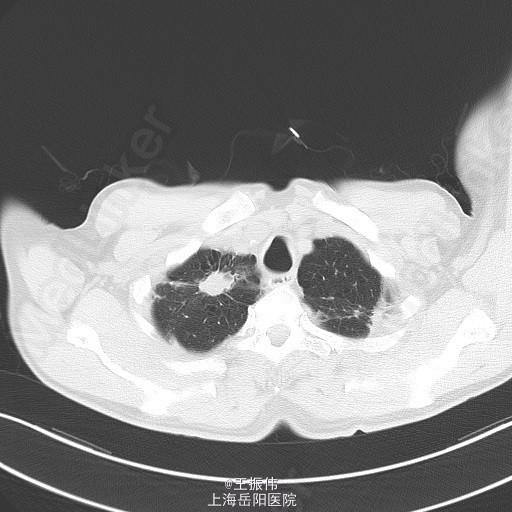

主诉、病史:老年男性,咳嗽咳痰15天,患者15日前因受凉后出现咳嗽,咳黄脓痰,自觉有发热,未测体温,6月25日至我院查血常规:白细胞:7.7*10^9/L,血红蛋白:106g/L,血小板:149*10^9/L,中性粒细胞:68.7,胸部CT:右肺上叶占位灶,两肺小结节灶,纵膈淋巴结增大,左肺下叶、右肺中叶炎症;两肺气肿伴肺大泡。自服止咳中成药(具体不详)后无明显好转。6月27日至地段医院就诊,予头孢羟氨苄片、金荞麦片、强力枇杷露,未见明显好转。

气管居中,颈静脉正常,胸廓两侧对称,无桶状胸,呼吸运动两侧对称,呼吸频率20次/分,肋间隙正常,无胸膜摩擦感。两肺叩诊清音,右肺可闻及湿性啰音,胸部CT:右肺上叶占位灶,两肺小结节灶,纵膈淋巴结增大,左肺下叶、右肺中叶炎症;两肺气肿伴肺大泡。组织病理【z155818】:灰白组织2粒,直径0.1cm。诊断:(左肺下叶开口)肉芽肿性炎,结核可能,请临床做相关病原体检测。支气管镜痰涂片:找到抗酸杆菌。